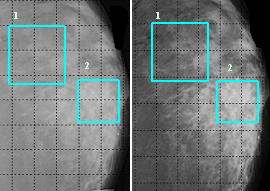

Рисунок 1 представляет

маммограммы удаленной молочной железы, полученные на разных энергиях излучения,

с выделенными двумя участками: 1-й участок

здоровой ткани, 2-й – раковой

опухоли. На основе данных маммограмм реконструировалось распределение

эффективного атомного номера.

Рис. 1.

Традиционные маммограммы, а – Е= 40 кэВ, б – 20 кэВ

1- участок со здоровой тканью,

2- участок с раковой опухолью.